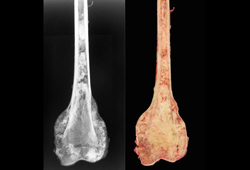

Osteossarcoma

Osteossarcoma osteoblástico do fêmur distal (radiografia e fotografia do espécime macroscópico)

Do acervo do Dr. Michael J. Klein e da Dra. Luminita Rezeanu